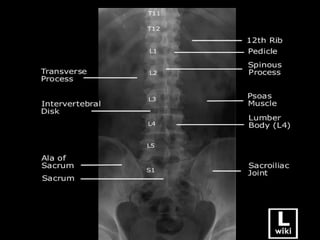

La colonne vertebrale = le RACHIS

RACHIS LOMBAIRE